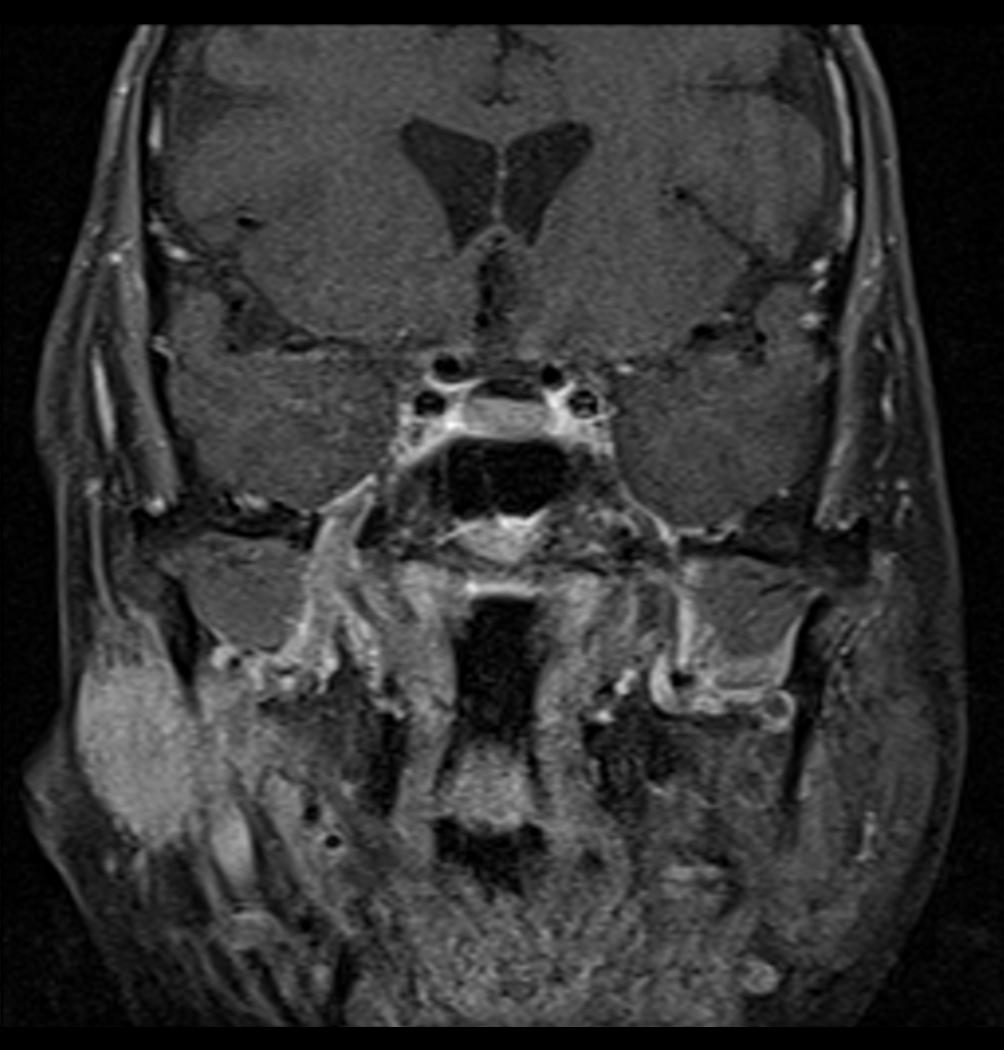

침샘암 진단에는 다양한 방법이 사용된다. 신체 검사 및 병력 청취를 통해 전반적인 건강 상태를 확인하고, 내시경 검사로 입 안, 인후 등을 관찰한다. 또한, MRI, CT, 방사선 사진, 초음파와 같은 영상 검사를 통해 종양 유무 및 전이 여부를 확인하며, 필요한 경우 생검을 실시하여 암세포를 확인한다.

3. 3. 영상 검사

침샘암의 유형과 양성/악성 여부를 판단하기 위해 다양한 영상 검사 방법이 사용된다.3. 4. 생검